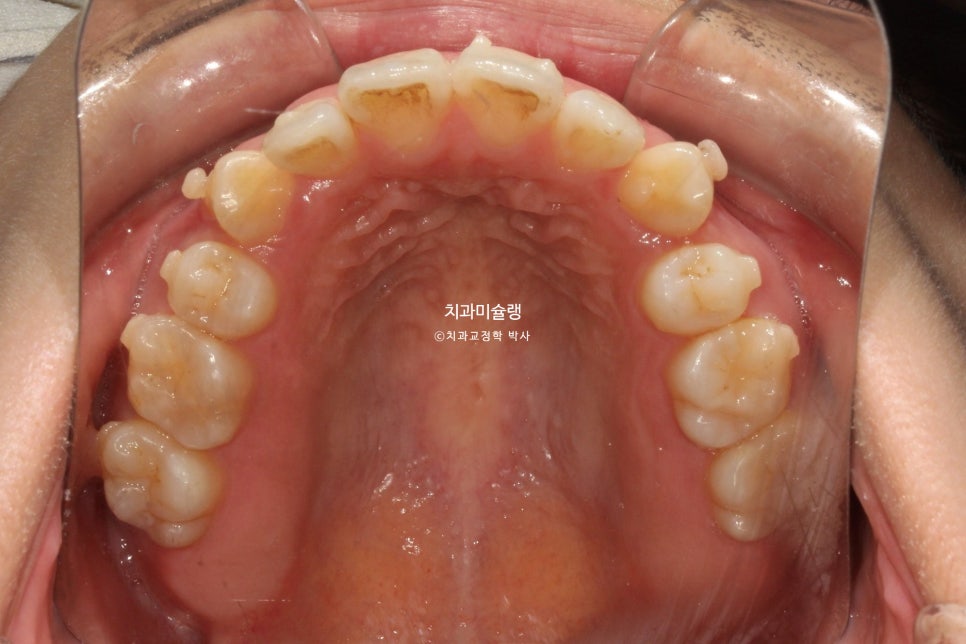

초진 시 환자 상태

2023년 9월 내원

덧니와 개방교합 때문에 오신 환자분 입니다.

덧니가 상당히 심한편입니다.

앞니뿐 아니라 작은어금니까지 또있는 개방교합입니다.

어금니 교합관계는 2급 입니다.

덧니를 제자리 시키려면 발치가 필수적인 상황입니다만

입매를 보면 하관에서 인중이 차지하는 비율이 크고 입술이 얇습니다.